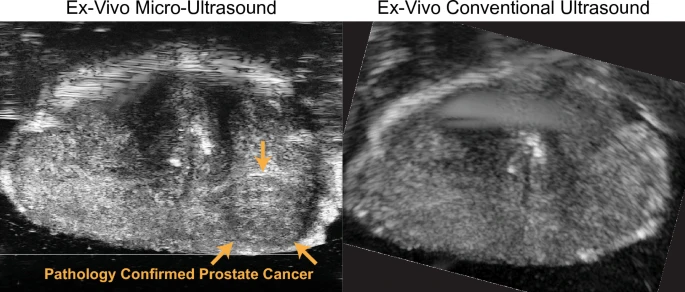

Perhaps one of the most game-changing recent developments in prostate ultrasound is the advent of micro-ultrasound, an ultra-high-frequency imaging approach. Traditional transrectal ultrasound operates in the ~6–12 MHz frequency range, which gives axial resolution on the order of 0.3–0.5 mm. Micro-ultrasound systems use much higher frequencies (often Twenty9 MHz, as with the ExactVu™ micro-ultrasound platform) to achieve resolutions around 70 microns (0.07 mm), which is about 3 times finer than standard TRUS. This high resolution can potentially allow direct visualization of prostate tumor lesions that were previously too small or subtle to see.

The concept is that micro-ultrasound might detect cancers as hypoechoic or irregular areas with much greater detail. Indeed, early clinical studies have been very promising. Micro-ultrasound can identify suspicious regions in real time during an ultrasound exam. To standardize this, a risk scoring system called PRI-MUS™ (Prostate Risk Identification using Micro-Ultrasound) was developed, analogous to the PI-RADS system on MRI. PRI-MUS uses a 1–5 scale based on micro-US findings (with 5 being highly suspicious). For example, a PRI-MUS 5 lesion might be an irregular hypoechoic area with shadowing in the peripheral zone on micro-US.

A meta-analysis in 2019 by Zhang et al. looked at micro-ultrasound’s accuracy for clinically significant cancer. It included 7 studies (769 patients) and found pooled sensitivity of 91% and specificity of 49% for micro-ultrasound in detecting clinically significant prostate cancer. The high sensitivity (~91%) is particularly notable – it rivals MRI’s sensitivity. The specificity was modest, indicating quite a few false positives (many suspicious areas on micro-US will turn out benign, hence the lower specificity). However, from a clinical standpoint, a high sensitivity is desirable in screening imaging; specificity can be managed by confirming with targeted biopsy. These results led the authors to conclude that “micro-ultrasound has superior ability to diagnose clinically significant prostate cancer” and is a convenient, cost-effective method for real-time imaging during biopsy.

Subsequent comparative studies have directly pitted micro-ultrasound against mpMRI. For instance, in a 2021 study (Guglietta et al.), micro-US and MRI were independently done and then targeted biopsies performed. They found that micro-ultrasound had detection rates on par with MRI for significant cancers. Another trial reported micro-US detected 94% of clinically significant cancers vs 90% for MRI in the same cohort. A 2024 study by Pensa et al. (Scientific Reports) used whole-mount prostatectomy specimens for ground truth and found micro-ultrasound achieved equivalent performance to retrospective MRI review for index lesion detection (91.7% vs 80%), and even detected tumor extent better, though MRI had fewer false positives per patient. Notably, prospective MRI reading in that study underperformed retrospective (73% sensitivity), highlighting both the variability of MRI and the potential consistency of micro-US. These studies suggest that micro-ultrasound can fill the gap where MRI is not done, offering an immediate, in-office alternative for high-resolution imaging of the prostate.

The practical appeal of micro-ultrasound is that it keeps the imaging and biopsy in the urologist’s office workflow. The ExactVu micro-ultrasound, for example, can toggle between conventional 12 MHz and 29 MHz modes. A urologist can scan the prostate, identify a PRI-MUS 4 or 5 region, and target that for biopsy in the same session, without needing prior MRI. This democratizes advanced imaging – no need to schedule MRI or have a radiologist interpret it; the urologist can directly visualize concerning areas. Additionally, micro-US is real-time and can scan the entire gland systematically at high resolution.